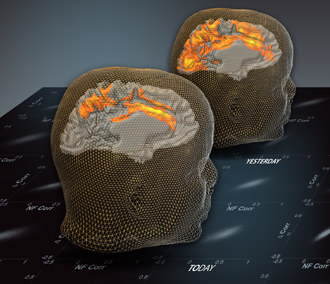

Weizmann Institute researchers say scientists can probe the brain and uncover the history of past experiences.